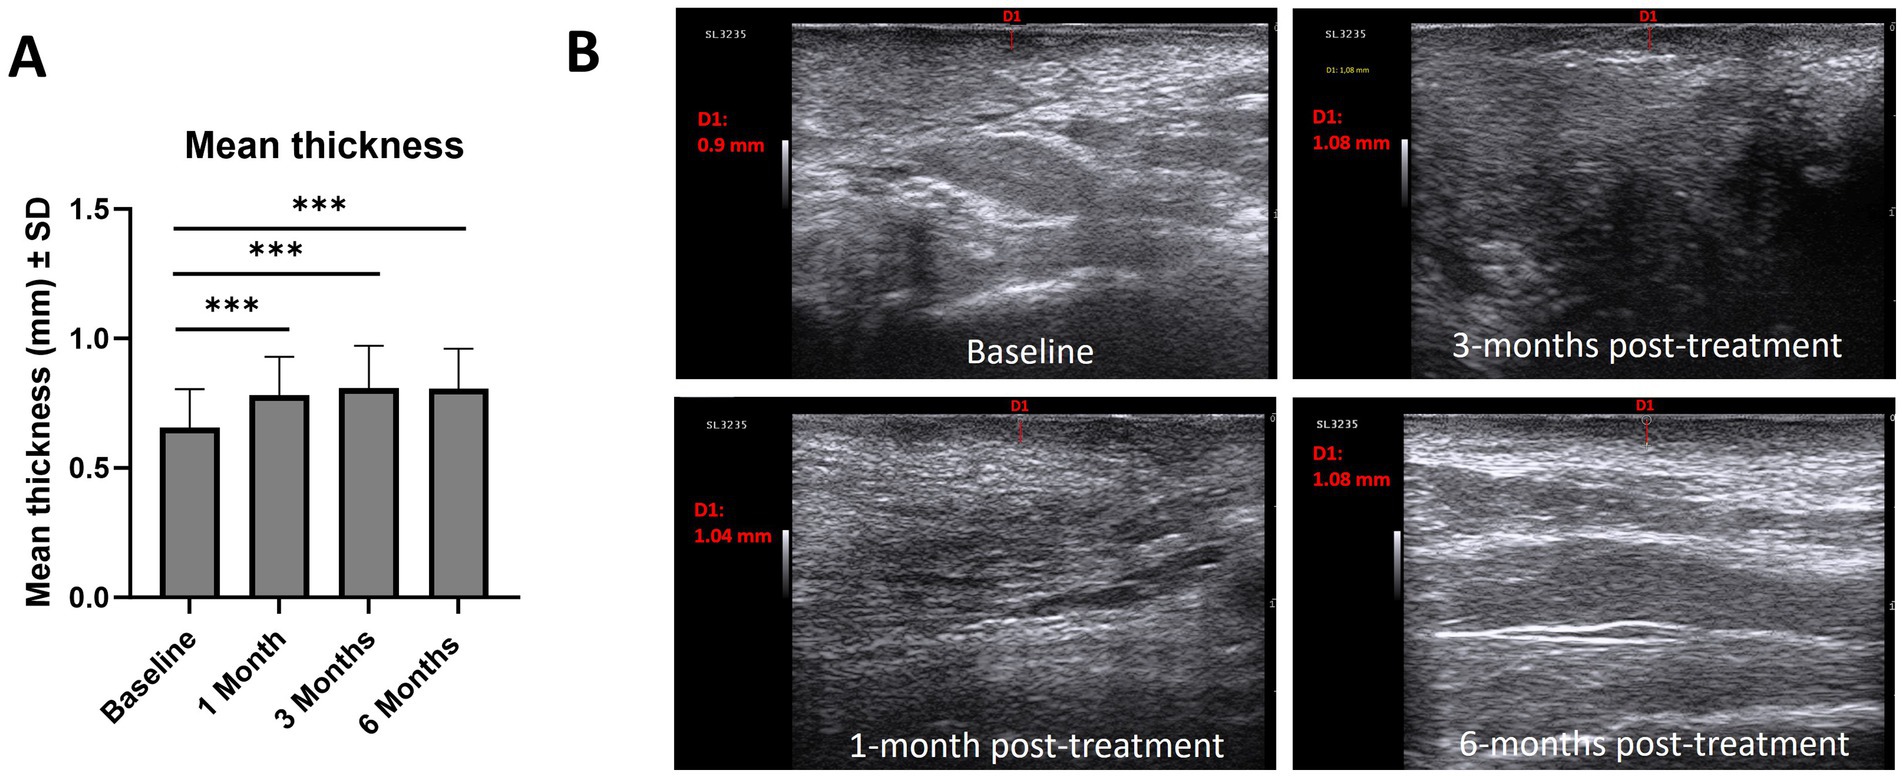

3.4 Ultrasound evaluation of the hypoechoic band

The thickness of the hypoechoic band of the dermal-epidermal junction increased from baseline (0.66 mm) at 1-month (0.78 mm; p < 0.001), 3-months (0.80 mm; p < 0.001) and 6-months post-treatment (0.80; p < 0.001) (Figure 5A). Regarding epidermal morphology of the hypoechoic band, the proportion of patients with smooth morphology increased after treatment, while irregular morphology decreased [baseline (smooth/irregular, 7%/93%), 1-month post-treatment (40%/60%), 3-months post-treatment (67%/33%), 6-months post-treatment (73%/27%)]. Similarly, the homogeneity of the of the hypoechoic band increased after treatment [baseline (homogeneous/non-homogeneous, 0%/100%), 1-month post-treatment (40%/60%), 3-months post-treatment (67%/33%), 6-months post-treatment (47%/53%)]. Figure 5B provides illustrative ultrasound images which indicate an increase in hypoechoic band thickness from baseline compared with 1-month and 3-months post-treatment.

(A) Mean thickness (mm, ± SD) of the hypoechoic band of the dermal-epidermal junction and ultrasound images of the hypoechoic band, (B). Example of 3 ultrasound measurements of hypoechoic band thickness. Analysis conducted using Wilcoxon matched-pairs signed rank test: *p < 0.05, **p < 0.01, ***p < 0.001. SD, standard deviation.

Non-invasive assessment is important for VLS, providing dermatologists with morphological information as well as measurable parameters (18). In this study, non-invasive ultrasound evaluation indicated increases in thickness of the hypoechoic band of the dermal-epidermal junction and increasing smooth morphology and homogeneity at 1-month, 3-months and 6-months post-treatment versus baseline. Although beyond the scope of this study, assessing the correlation between hypoechoic band thickness and inflammatory cell infiltration depth in histopathology represents an area for future research for studies of HCC of HA for the management of VLS (18). Furthermore, while significant improvements in some disease features were observed in this study (scales, hyperkeratosis and purpuric lesions, abrasions or erosions at baseline), the sample size was limited to the number of patients with a specific disease feature at baseline. In future studies, enrolling a larger number of patients with a pre-defined disease feature will provide greater statistical power to assess treatment effects.